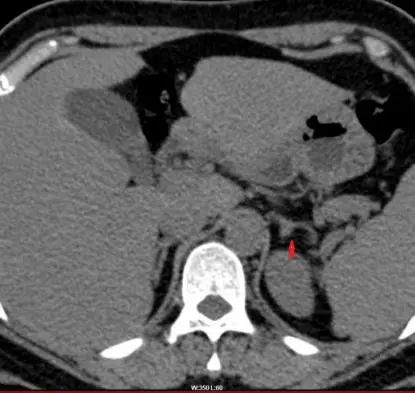

30岁的李女士(化名)因“高血压”入住新医大一附院高血压科,通过完善肾上腺CT检查提示左侧肾上腺增生,并呈现明显高醛固酮及低肾素表现,符合原发性醛固酮增多症诊断,但由于李女士肾上腺无明显占位,结合李女士的病情,高血压科谢翔教授决定为其采取经肘静脉入路行双侧肾上腺静脉同步取血术进行AVS分型诊断。

肾上腺CT